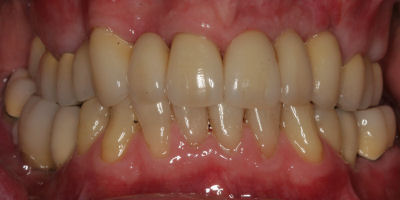

This is an advanced set of dental procedures best carried out by prosthodontists or restorative dentists. Full mouth rehabilitation is a term used in dentistry for rebuilding teeth and supporting structures after decay and gum disease has been stabilised. Full mouth rehabilitation is only required if your bite has collapsed or you have multiple missing or heavily filled teeth. Implants, crown and bridgework and/or partial or full dentures can be used to restore your bite close to its original height. Temporary restorations or dentures are used to get an idea of what the final result will be like before having the final restorations made. Temporary restorations also allow you to have input into your appearance and smile giving you the opportunity to show friends and family what your teeth may look like when the work is complete.

Before/After